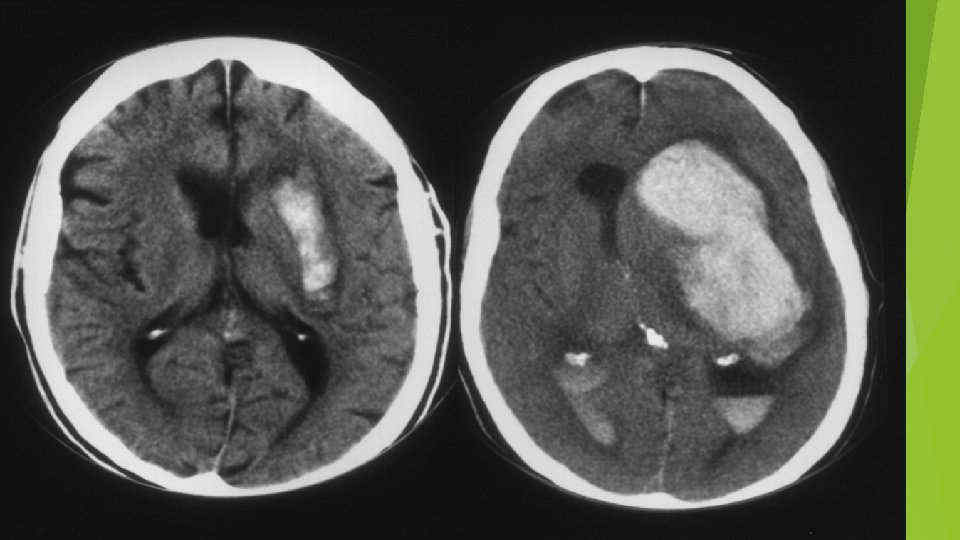

CLASSIFICATION Ischemic Stroke 87% 80% thrombotic 20% embolic Hemorrhagic Stroke 13% 97% intracerebral 3% subdural

IMAGING CT…reliable for intracranial hemorrhage close to 100% sensitive not sensitive for ischemic CVA…especially early MRI…diffusion weighted hyperdense regions of ischemia can detect ischemia after 5 -10 minutes time consuming…. cooperation issues ECHO…echocardiography can identify source of cerebral emboli identify patent foramen ovale

Treatment of Complications Brain edema/Increased ICP…peaks 3 -4 days after CVA restriction free water avoid excess glucose minimize hypoxemia and hypercarbia treat hyperthermia elevate HOB 20 -30 degrees avoid antihypertensive agents causing cerebral vasodilation Treatment of increased ICP hyperventilation, hypertonic saline, osmotic diuretics Interventricular CSF drainage Steroids not recommended decompressive surgery…effective…decisions based on volume of tissue infarcted and midline shift